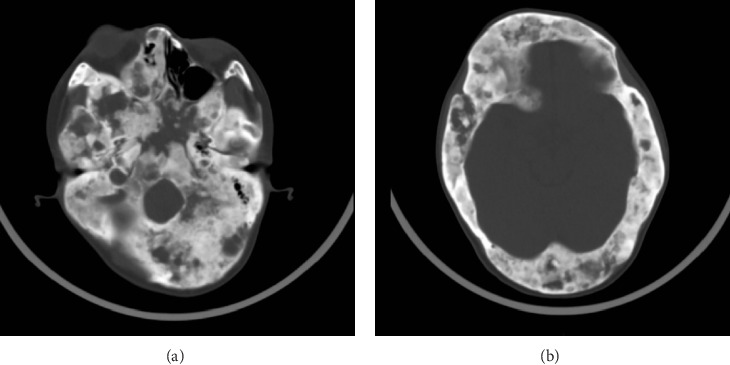

Background: Fibrous dysplasia (FD) is a rare congenital bone disease. Denosumab, a monoclonal antibody targeting nuclear factor kappa-B ligand (RANKL), suppresses osteoclast activity and exhibits therapeutic potential for FD. Case Presentation: We present the case of an adult female patient diagnosed with FD who had undergone 7 treatment cycles of denosumab (120 mg/dose, sc.) with a cumulative dose of 840 mg. After discontinuing denosumab for 7 months, the patient experienced a crisis of rebound hypercalcemia. Conclusion: Although, rare reports of hypercalcemia induced by discontinuation of denosumab are primarily seen in adolescents. By reporting this case, we aim to alert clinicians to the risk of rebound hypercalcemia in adult patients with FD undergoing denosumab treatment.